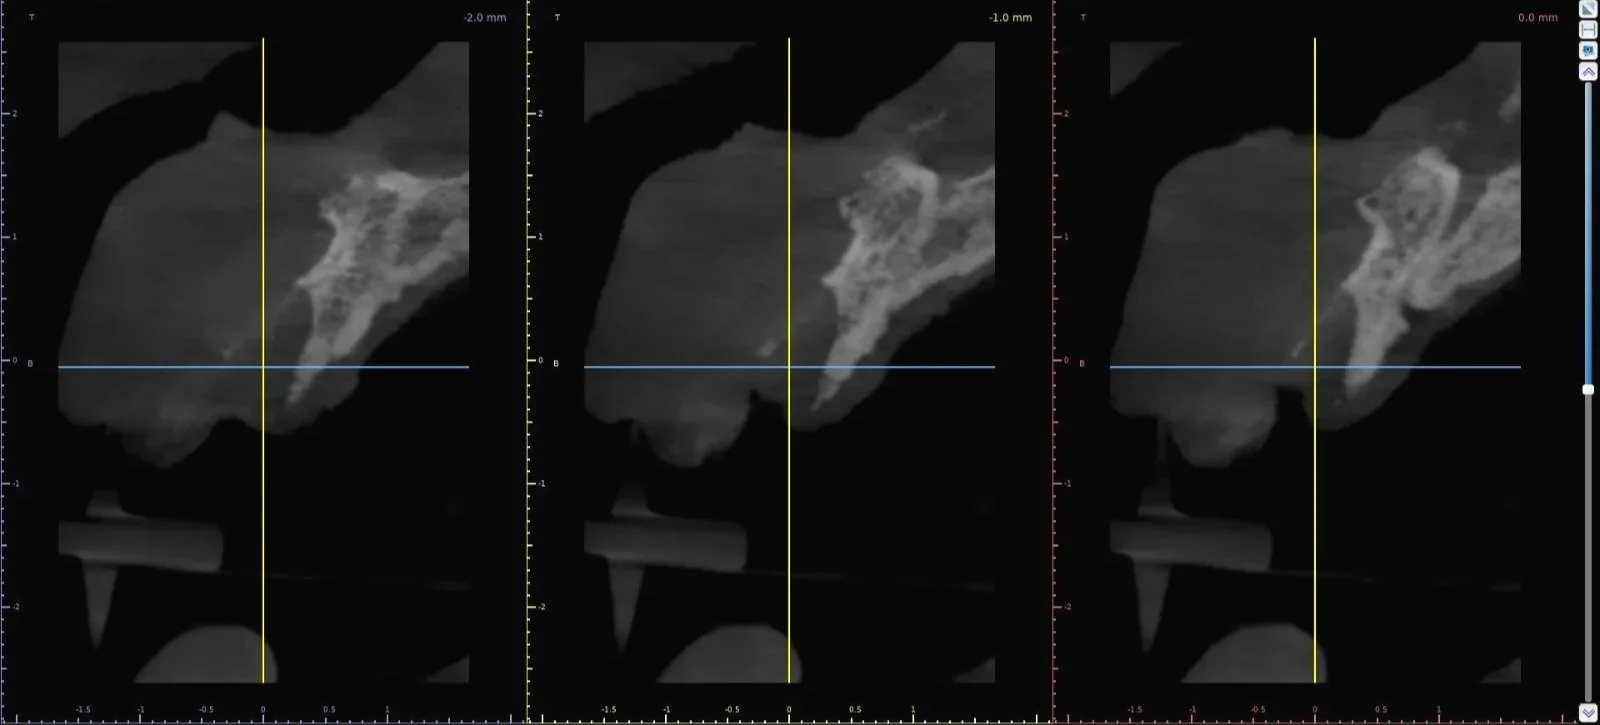

Tomografía previa